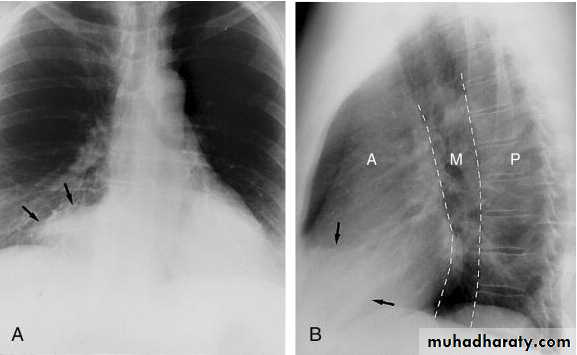

Pleural Effusion on Chest Radiographs.

Posteroanterior (A) and lateral (B) chest radiographs demonstrate the typical meniscoid appearance (arrows) in a patient with a left pleural effusion